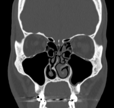

Deviazione del setto nasale

Il 90% circa della popolazione presenta un setto nasale deviato. Tuttavia molte persone con tale condizione non presenta disturbi respiratori. La correzione di una deviazione settale richiede un intervento chirurgico di settoplastica, associata spesso a turbinoplastica. Tale procedura è indicata nei casi in cui la deviazione del setto nasale provochi sintomi respiratori importanti e siano stati esclusi altre cause di ostruzione nasale (es. riniti croniche)